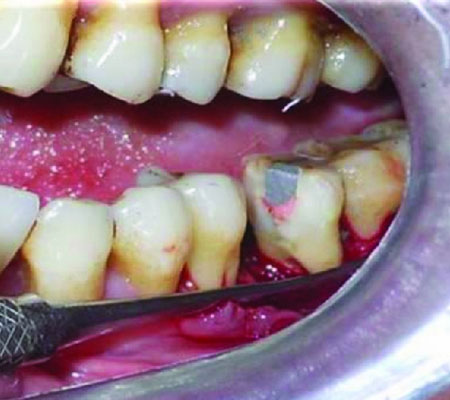

Hemisection

The surgical separation of a multirooted tooth, especially a mandibular molar, through the furcation in such a way that a root and the associated portion of the crown may be removed.